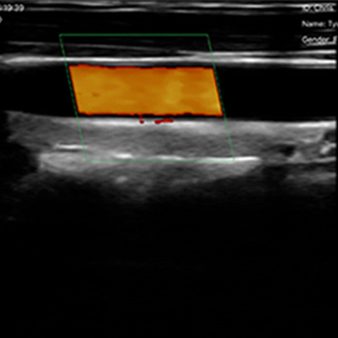

El escáner de ultrasonido portátil de doble sonda es una solución avanzada diseñada para ofrecer máxima versatilidad clínica en un solo dispositivo. Gracias a su tecnología integrada, combina tres modos de escaneo —convexo, lineal y phased array— permitiendo evaluar estructuras profundas, tejidos superficiales y realizar estudios cardíacos con alta precisión. Esta integración reduce significativamente los costos al reemplazar la necesidad de adquirir múltiples sondas por separado.

| Modo de escaneo | B, B/M, Color, PW |

B, B/M, Color, PW

Asistencia en punción

Línea guía en plano

Línea guía fuera de plano

Mejora de aguja